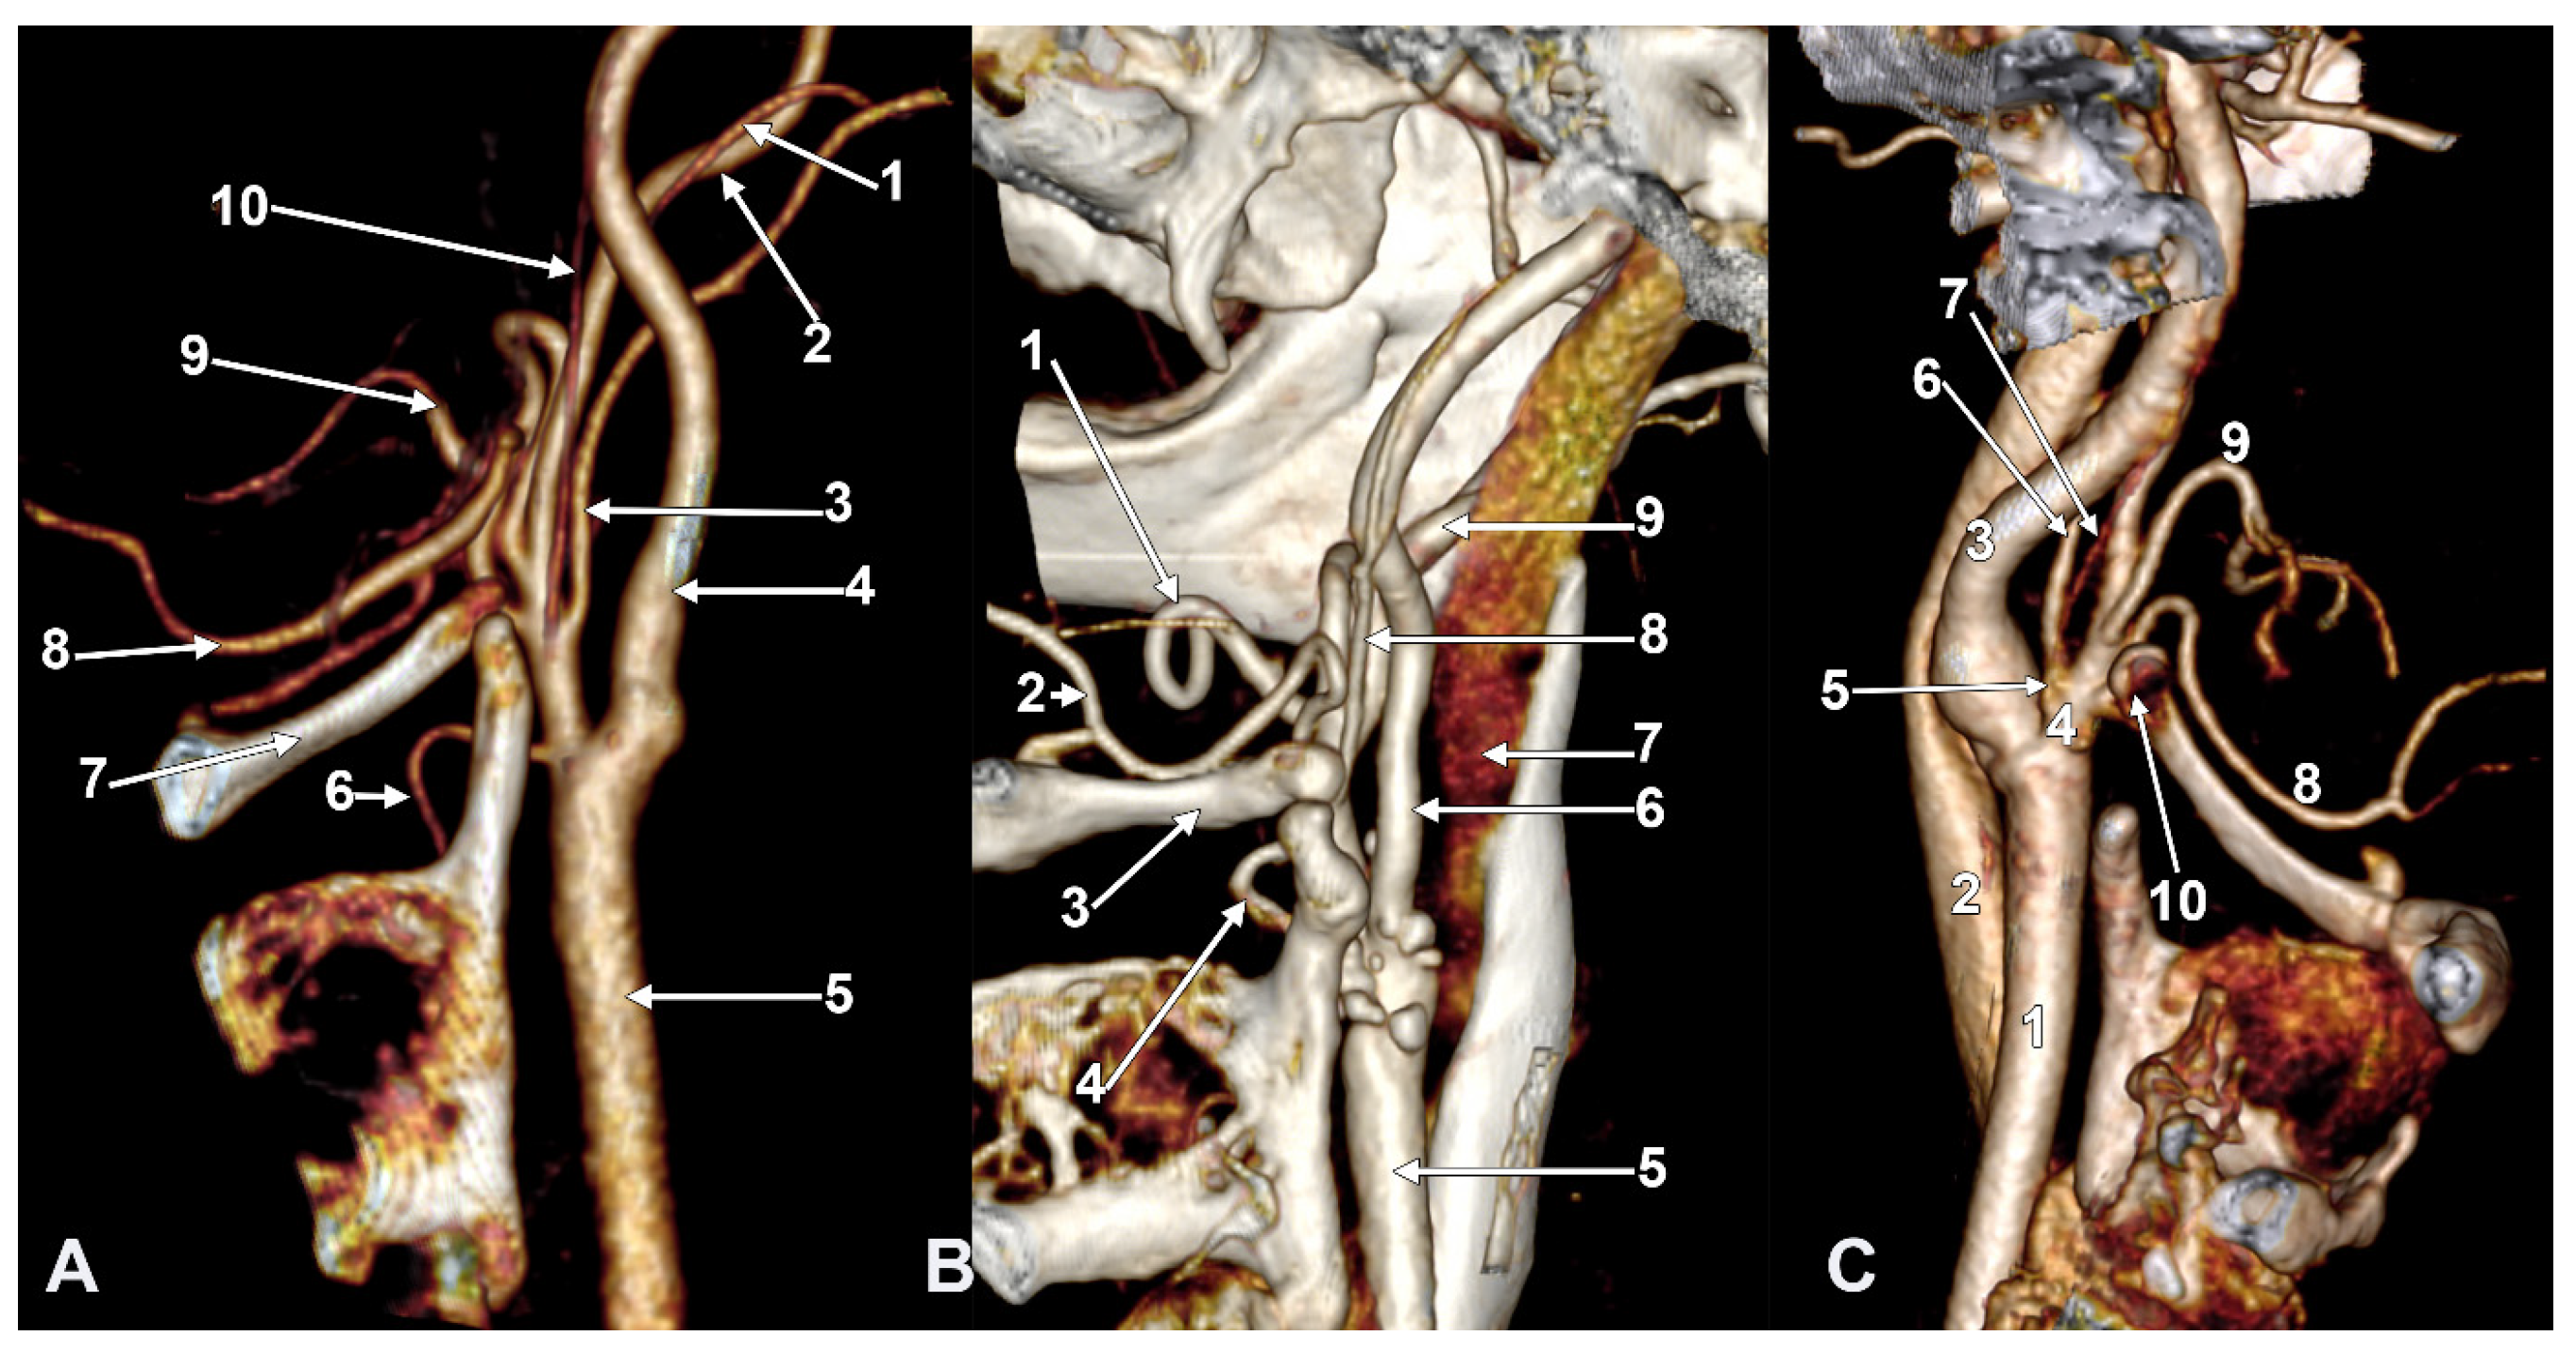

Figure 11. Type V ascending pharyngeal artery originating from the carotid bifurcation. Superior laryngeal artery with suprahyoid origin. Three-dimensional rendering. Left side. (A) Lateral view. (B) Medial view. 1. Common carotid artery; 2. internal carotid artery; 3. external carotid artery; 4. styloid process; 5. superior thyroid artery; 6. superior laryngeal artery; 7. ascending pharyngeal artery; 8. occipital artery; 9. lingual artery; 10. facial artery; 11. maxillary artery; 12. superficial temporal artery; 13. transverse facial artery; 14. thyroid cartilage; 15. greater hyoid horn; 16. sternocleidomastoid branch; 17. descending branch; 18. posterior branch.

3.7. The S40 Type of the Origin of the External Carotid Artery’s Branches

In one of the studied cases, we found, on the left side, an unexpected arterial variant, corresponding to the type S40 (STA/APA from the CB, OA/SCM br.-LA). The CB was subgonial, 1.82 cm posterosuperior to the hyoid tubercle. From the medial aspect of the CB, the left two branches were as follows: one descending—the STA, and the other ascending—the APA (Figure 11). The ECA and ICA made an angle of 62.39°, opened superiorly. The initial segment of the ECA, 1.53 cm long, was directed anterosuperiorly, and then the ECA made an angle of 118.85°, opening posteriorly to further continue with the retromandibular course. At 6 mm distal to the origin of the STA and APA, the LA, OA, and a SCM branch originated from the ECA at the same level. The SCM branch originated from the lateral wall of the ECA, the AO from the inferomedial wall of the ECA, and the OA from the superolateral wall of the ECA. At 0.93 cm distally to the origin of the latter, the FA originated from the ECA.

The SCM branch traversed the venous fork between the common facial vein and the IJV, deep into the sternocleidomastoid.

The left STA had a 1.39 cm suprahyoid segment from which, 4 mm superior to the hyoid tubercle, the superior laryngeal artery arose. The latter described an ‘S’-shaped course, passing at 4.2 mm medial to the hyoid tubercle and then returning laterally, applied to the lateral aspect of the thyrohyoid membrane. The left ECA trifurcated into the maxillary, superficial temporal, and transverse facial arteries.